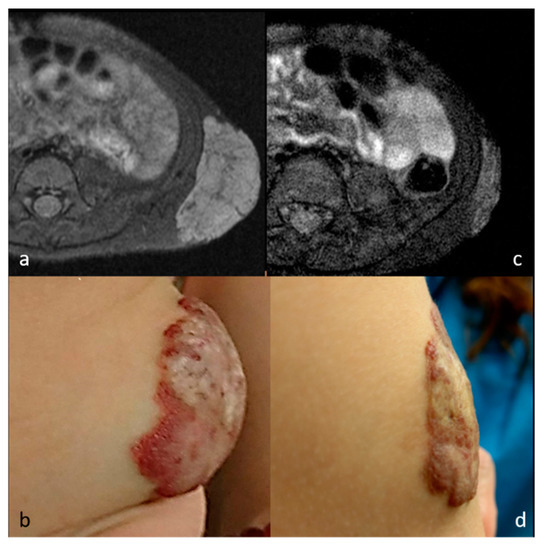

| 5 | 1 | F | Congenital Hemangioma | Left abdominal wall | US, MR | 28.8 | 5.0 | 12 | 82.6% | 4 | 3 | GA | 1 |

| 8 c | 7 | F | Congenital Hemangioma | Left buttock | US, MR | 15.4 | 10.2 | 6 | 33.8% | 4 | 4 | GA | 1 |